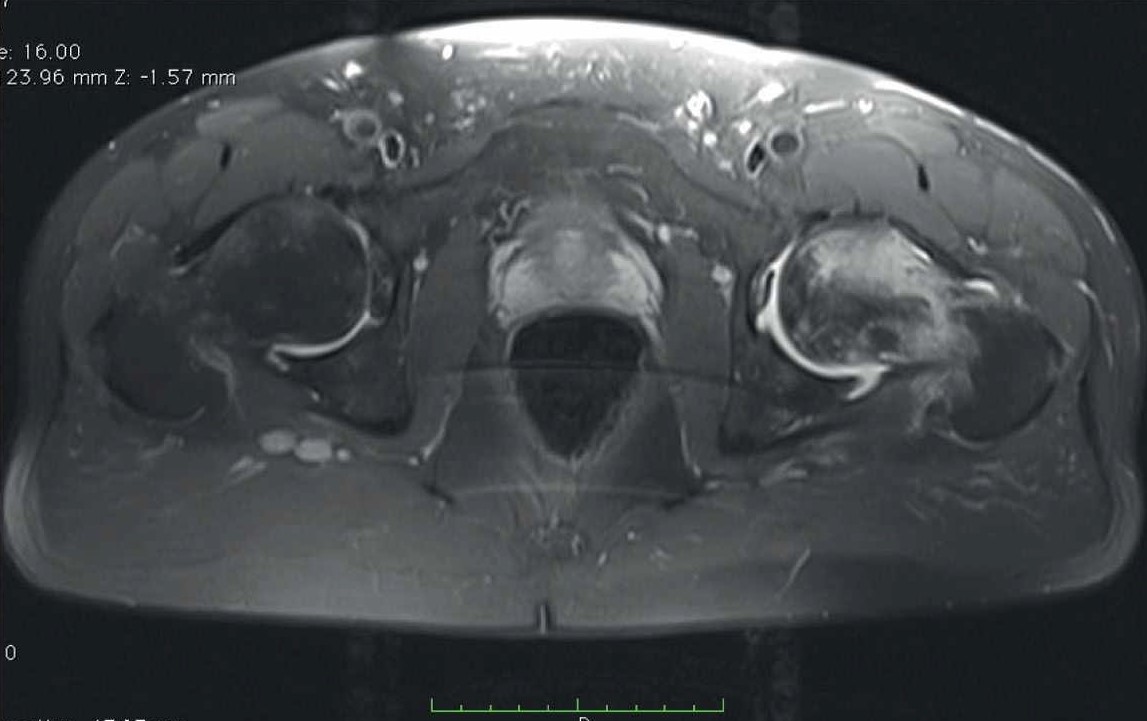

- Мужчина В., 36 лет, без отягощенного соматического и семейного анамнеза в августе 2021 г. перенес тяжелую форму COVID-19. Находился на стационарном лечении 17 дней. Пациенту назначали антикоагулянты (эноксапарин натрия 1,6 мл/сут на весь период лечения), противовирусный препарат фавипиравир (3600 мг – 1 сут, затем 1600 мг – 6 сут). В стационаре терапия дексаметазоном продолжена в дозировке 20 мг ежедневно с последующим снижением до 4 мг к моменту выписки – 272 мг (в пересчете на преднизолон – 1813 мг). После выписки из стационара принимал ривароксабан 15 мг/сут.

В декабре 2021 г. стала беспокоить боль распирающего характера в обоих тазобедренных суставах в покое, интенсивность боли снижалась при нагрузке, и в поясничном отделе позвоночника (6 баллов по ВАШ). Обратился к неврологу, и было начато консервативное лечение люмбалгии. В феврале 2022 г. вследствие неэффективности консервативного лечения и сохранения болевого синдром выполнена СКТ таза. Обнаружены двусторонний коксартроз, асептический некроз головок бедренных костей (рис. 3).

Рис. 3. СКТ таза у пациента В. Диагноз – двусторонний коксартроз, асептический некроз головок бедренных костей.

В связи с наличием субхондрального перелома головки правой бедренной кости пациенту выполнено тотальное эндопротезирование правого тазобедренного сустава.

В позднем послеоперационном периоде пациент отмечал восстановление функции правой нижней конечности, отсутствие болевого синдрома (0 баллов по ВАШ) в правом тазобедренном суставе